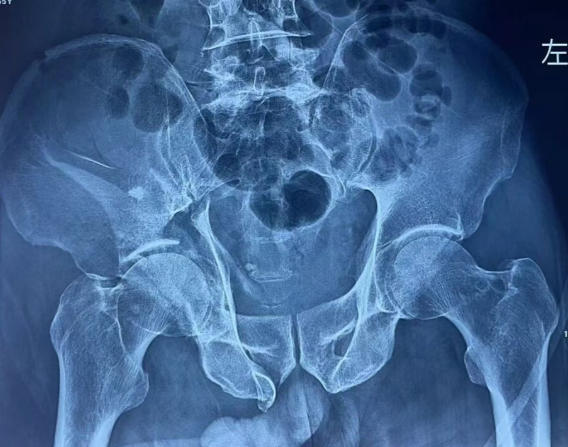

术前